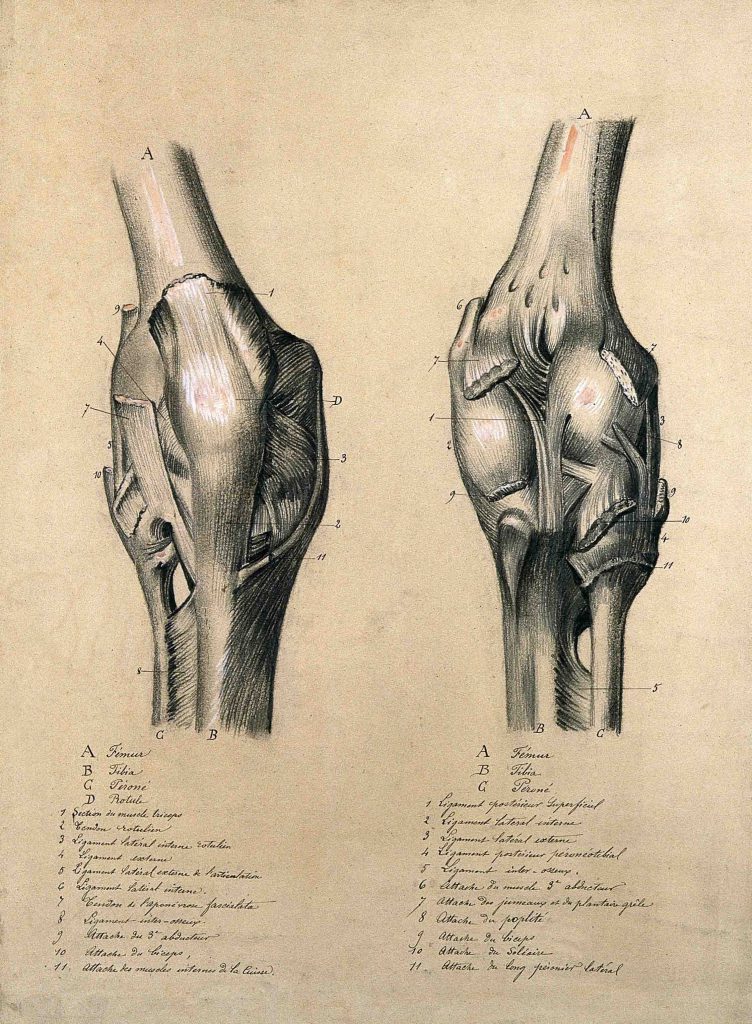

مفصل زانو از جمله پیچیدهترین و در عین حال پرکاربردترین مفاصل بدن انسان است. این مفصل بهعنوان یک مفصل لولایی (hinge joint) عمل میکند که اجازه خم و راست شدن (فلکشن و اکستنشن) را میدهد، اما برخلاف مفاصل ساده، ترکیبی از حرکات چرخشی و لغزشی نیز در آن صورت میگیرد که برای انجام دقیق و هماهنگ حرکات روزمره ضروری است.

اجزای اصلی مفصل زانو

- استخوانها:

- استخوان ران (Femur): بزرگترین استخوان بدن که از بالا وارد مفصل زانو میشود.

- درشتنی (Tibia): استخوان اصلی ساق پا که وزن بدن از طریق آن به پایین منتقل میشود.

- کشکک (Patella): استخوان کوچک و متحرکی که در جلوی زانو قرار دارد و درون تاندون عضله چهارسر ران (Quadriceps) جای گرفته است. این استخوان نقش حفاظتی داشته و به افزایش کارایی انقباض عضله کمک میکند.

- غضروفها:

- مینیسک داخلی و خارجی (Medial & Lateral Meniscus): دو لایه غضروفی نیمدایرهایشکل بین استخوان ران و درشتنی قرار دارند که به جذب ضربه، توزیع فشار و افزایش پایداری مفصل کمک میکنند.

- رباطها (Ligaments):

- رباط صلیبی قدامی (ACL) و خلفی (PCL): حرکت جلو و عقب استخوان درشتنی را نسبت به استخوان ران کنترل میکنند.

- رباطهای جانبی داخلی (MCL) و خارجی (LCL): از حرکات جانبی غیرطبیعی جلوگیری میکنند و پایداری زانو را حفظ میکنند.

- تاندونها (Tendons):

- تاندونهای عضلات چهارسر و همسترینگ، نیروی عضلات را به استخوان منتقل کرده و باعث حرکت مفصل زانو میشوند.

- تاندون کشککی (Patellar Tendon) که کشکک را به درشتنی متصل میکند.

- کیسههای زلالی (Bursae):

- کیسههای پر از مایع که برای کاهش اصطکاک میان استخوانها، تاندونها و پوست در اطراف زانو تعبیه شدهاند.